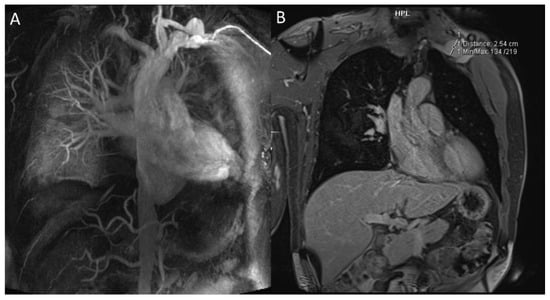

- Akpolat, T.; Danaci, M.; Belet, Ü.; Erkan, M.L.; Akar, H. MR Imaging and MR Angiography in Vascular Behçet’s Disease. Magn. Reson. Imaging 2000, 18, 1089–1096. [Google Scholar] [CrossRef]